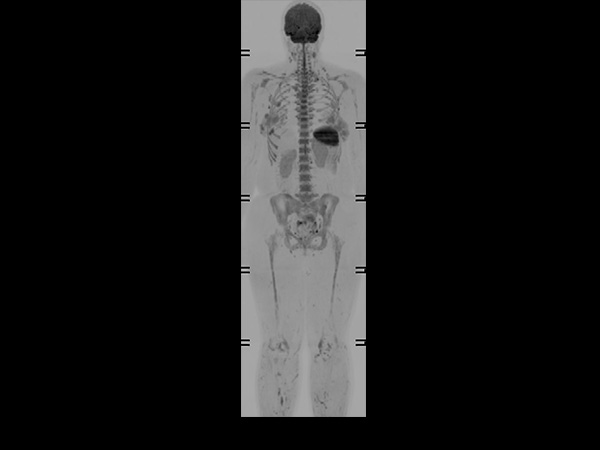

Helium-free MR operations: Wholebody imaging under 30 minutes